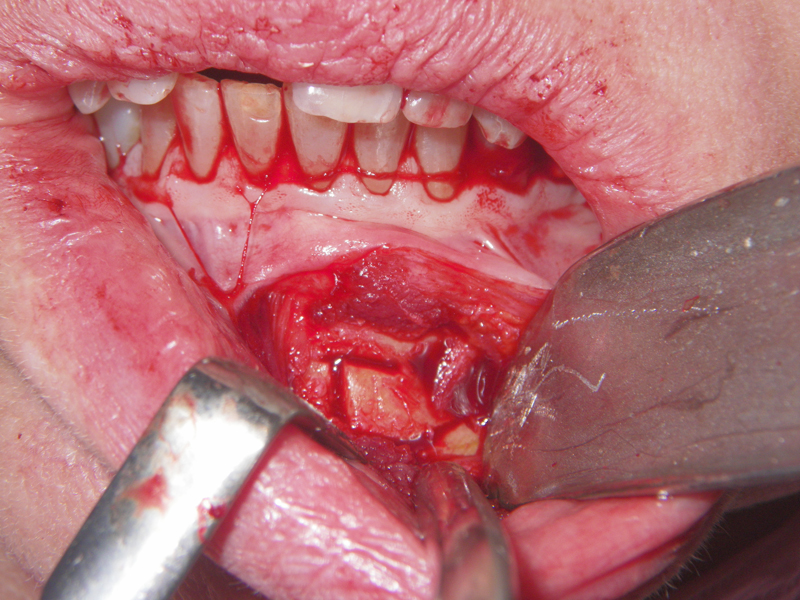

- Incision

- Identify, don’t ‘skeletonize,’ mental nerves

- Midline, lateral score marks

- Osteotomy 5 mm below tooth apices & mental nerve

- Angulation of cut (Depends on planned movement)

- Downfracture (release ‘wings’)

- Fixation (plate, screws, wire)

- Layered closure (mentalis)